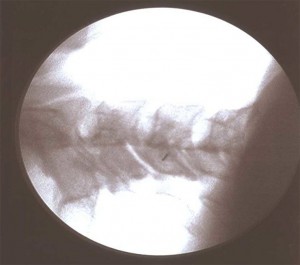

Con el paciente en decúbito prono con la cabeza en posición neutra y los brazos en dirección caudal se coloca el arco de fluoroscopia en posición anteroposterior y se localiza el espacio interlaminar seleccionado con ayuda de un marcador radiopaco. Se debe conseguir que las apófisis espinosas estén equidistantes entre los pedículos y que no exista un doble contorno en los cuerpos vertebrales. Para eliminar el doble contorno si existiera se debe de realizar u movimiento del arco de fluoroscopia en  dirección craneocaudal hasta que desaparezca. No se recomienda la punción en línea media por encima de C5 debido a la elevada incidencia de no fusión del ligamento amarillo. Una vez marcado el lugar de punción se inserta la aguja de Tuohy en visión túnel y dirección al punto diana, la entrada al espacio epidural se realiza  con la técnica de pérdida de resistencia. La técnica se puede realizar con suero, aire y gota pendiente. La elección de la técnica dependerá del entrenamiento de cada profesional con cada una de ellas. Cuando se alcanza el ligamento interespinoso, se rota el arco a posición lateral, para comprobar la profundidda de la aguja y minimizar el riesgo de punción dural. Como la visión lateral a nivel cervical es muy dificultosa por la superposición de las imágenes de los hombros, se utilizan proyecciones oblicuas y en esta posición la punta de la aguja no debe sobrepasar el borde anterior de la apófisis espinosa. Una vez localizado el espacio epidural se inyecta de 1-3ml de contraste radiopaco en tiempo real verificando la posición de la aguja y asegurándonos de que no nos encontramos en el interior de un vaso. Comprobamos nuevamente la distribución del contraste con el arco en posición anteroposterior visualizando el epidurograma y administramos un corticoide no particulado con el anestésico local. Finalmente se retira la aguja con el mandril.